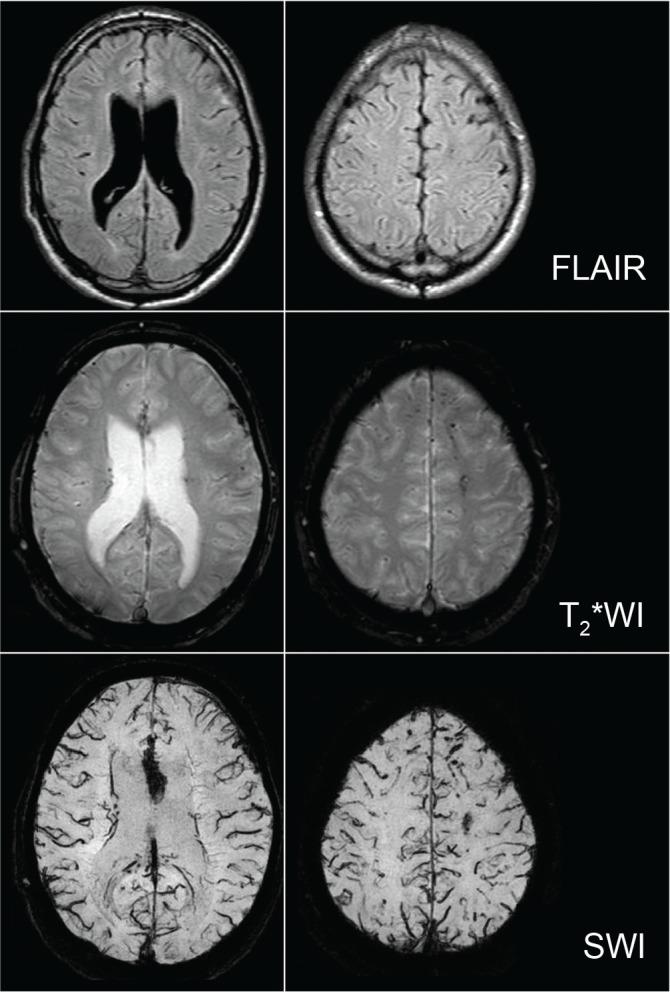

The diagnotic criteria for disorder of the executive function of the brain (DEFB) as a syndrome of sequela were administratively established (ad-DEFB) in Japan in 2006 to support disabled patients whose impairment, limited to cognition (memory, attention, execution, and behavior), emerges after organic brain injuries regardless of physical deficits. However, some patients suffering from traumatic brain injury (TBI) have been excluded from receiving medico-social services. In particular, this tendency is more prominent in patients with mild TBI because no lesions are apparent on conventional computed tomography (CT) or magnetic resonance imaging (MRI) in the chronic phase. Recent development of new MRI neuroimaging modalities and positron emission tomography (PET) imaging makes it possible to detect regions of minute organic lesions and metabolic dysfunction in the brain where organic lesions may be absent or cannot be detected on conventional CT or MRI. In this review, we discuss diagnostic criteria for mild TBI and ad-DEFB, the relationship between the two disorders, characteristic neuroimaging [(MRI and 18F-fluorodeoxyglucose-positron emission tomography (FDG-PET)] of diffuse brain injury including cerebral concussion, which is the principal cause of mild TBI, and suggested pathological mechanisms of ad-DEFB in DBI.

2006年,日本行政管理部门制定了脑执行功能障碍(DEFB)后遗症综合征的诊断标准(ad-DEFB),以支持那些在器质性脑损伤后出现认知障碍(记忆、注意力、执行能力和行为)但无身体缺陷的残疾患者。然而,一些创伤性脑损伤(TBI)患者被排除在接受医疗社会服务之外。特别是在轻度TBI患者中这种趋势更为明显,因为在慢性期常规计算机断层扫描(CT)或磁共振成像(MRI)上没有明显病变。新的MRI神经成像技术和正电子发射断层扫描(PET)成像的最新发展使得检测大脑中微小器质性病变区域和代谢功能障碍成为可能,而这些区域在常规CT或MRI上可能不存在或无法检测到。在这篇综述中,我们讨论了轻度TBI和ad-DEFB的诊断标准、这两种疾病之间的关系、包括脑震荡(轻度TBI的主要原因)在内的弥漫性脑损伤的特征性神经成像[MRI和18F-氟脱氧葡萄糖-正电子发射断层扫描(FDG-PET)],以及DBI中ad-DEFB的推测病理机制。